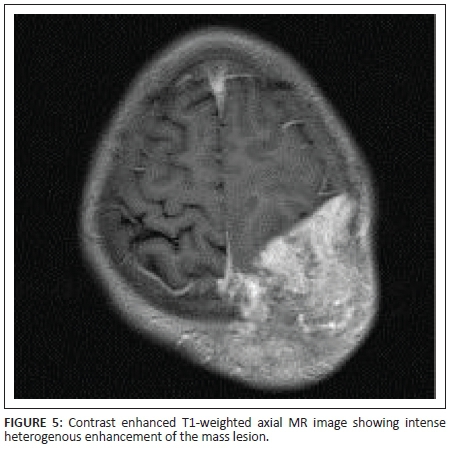

X-rays of the skull showed a well-defined lytic lesion in the left parietal bone with an associated large soft tissue component. No marginal sclerosis or periosteal reaction was noted (Figure 1a and 1b). Non-contrast computed tomography (NCCT) revealed a well-defined heterogeneous hyperdense mass lesion centred on the left parietal bone causing bone destruction, compressing the adjacent brain parenchyma and bulging into the scalp. A few small bony fragments were seen at the periphery of the lesion (Figure 2). Magnetic resonance imaging (MRI) of the brain with contrast demonstrated a well-defined heterogeneously enhancing soft tissue mass lesion measuring 8.0 cm × 7.9 cm × 6.8 cm causing destruction of the left parietal bone and bulging into the scalp. Some flow voids were seen with the mass. No restricted diffusion or surrounding oedema was noted. There was mass effect with compression of adjacent brain parenchyma and mild midline shift to the right side. The mass was compressing adjacent superior sagittal sinus but not invading it (Figures 3, 4, 5 and 6). Skeletal survey of the body revealed no other lytic lesions anywhere in the body.

On radiography, SPB presents as a well-defined osteolytic lesion with clear margins and narrow zone of transition. There is no bony sclerosis or periosteal reaction. The lesion is hyperdense on NCCT and shows marked homogenous enhancement with contrast. Small bony fragments may be seen at the periphery. On MRI, SPB appears isointense on T1-weighted images and hyperintense on T2-weighted images. Intratumoural flow voids have been described. The lesion shows dense but heterogeneous enhancement with contrast.3,5,6